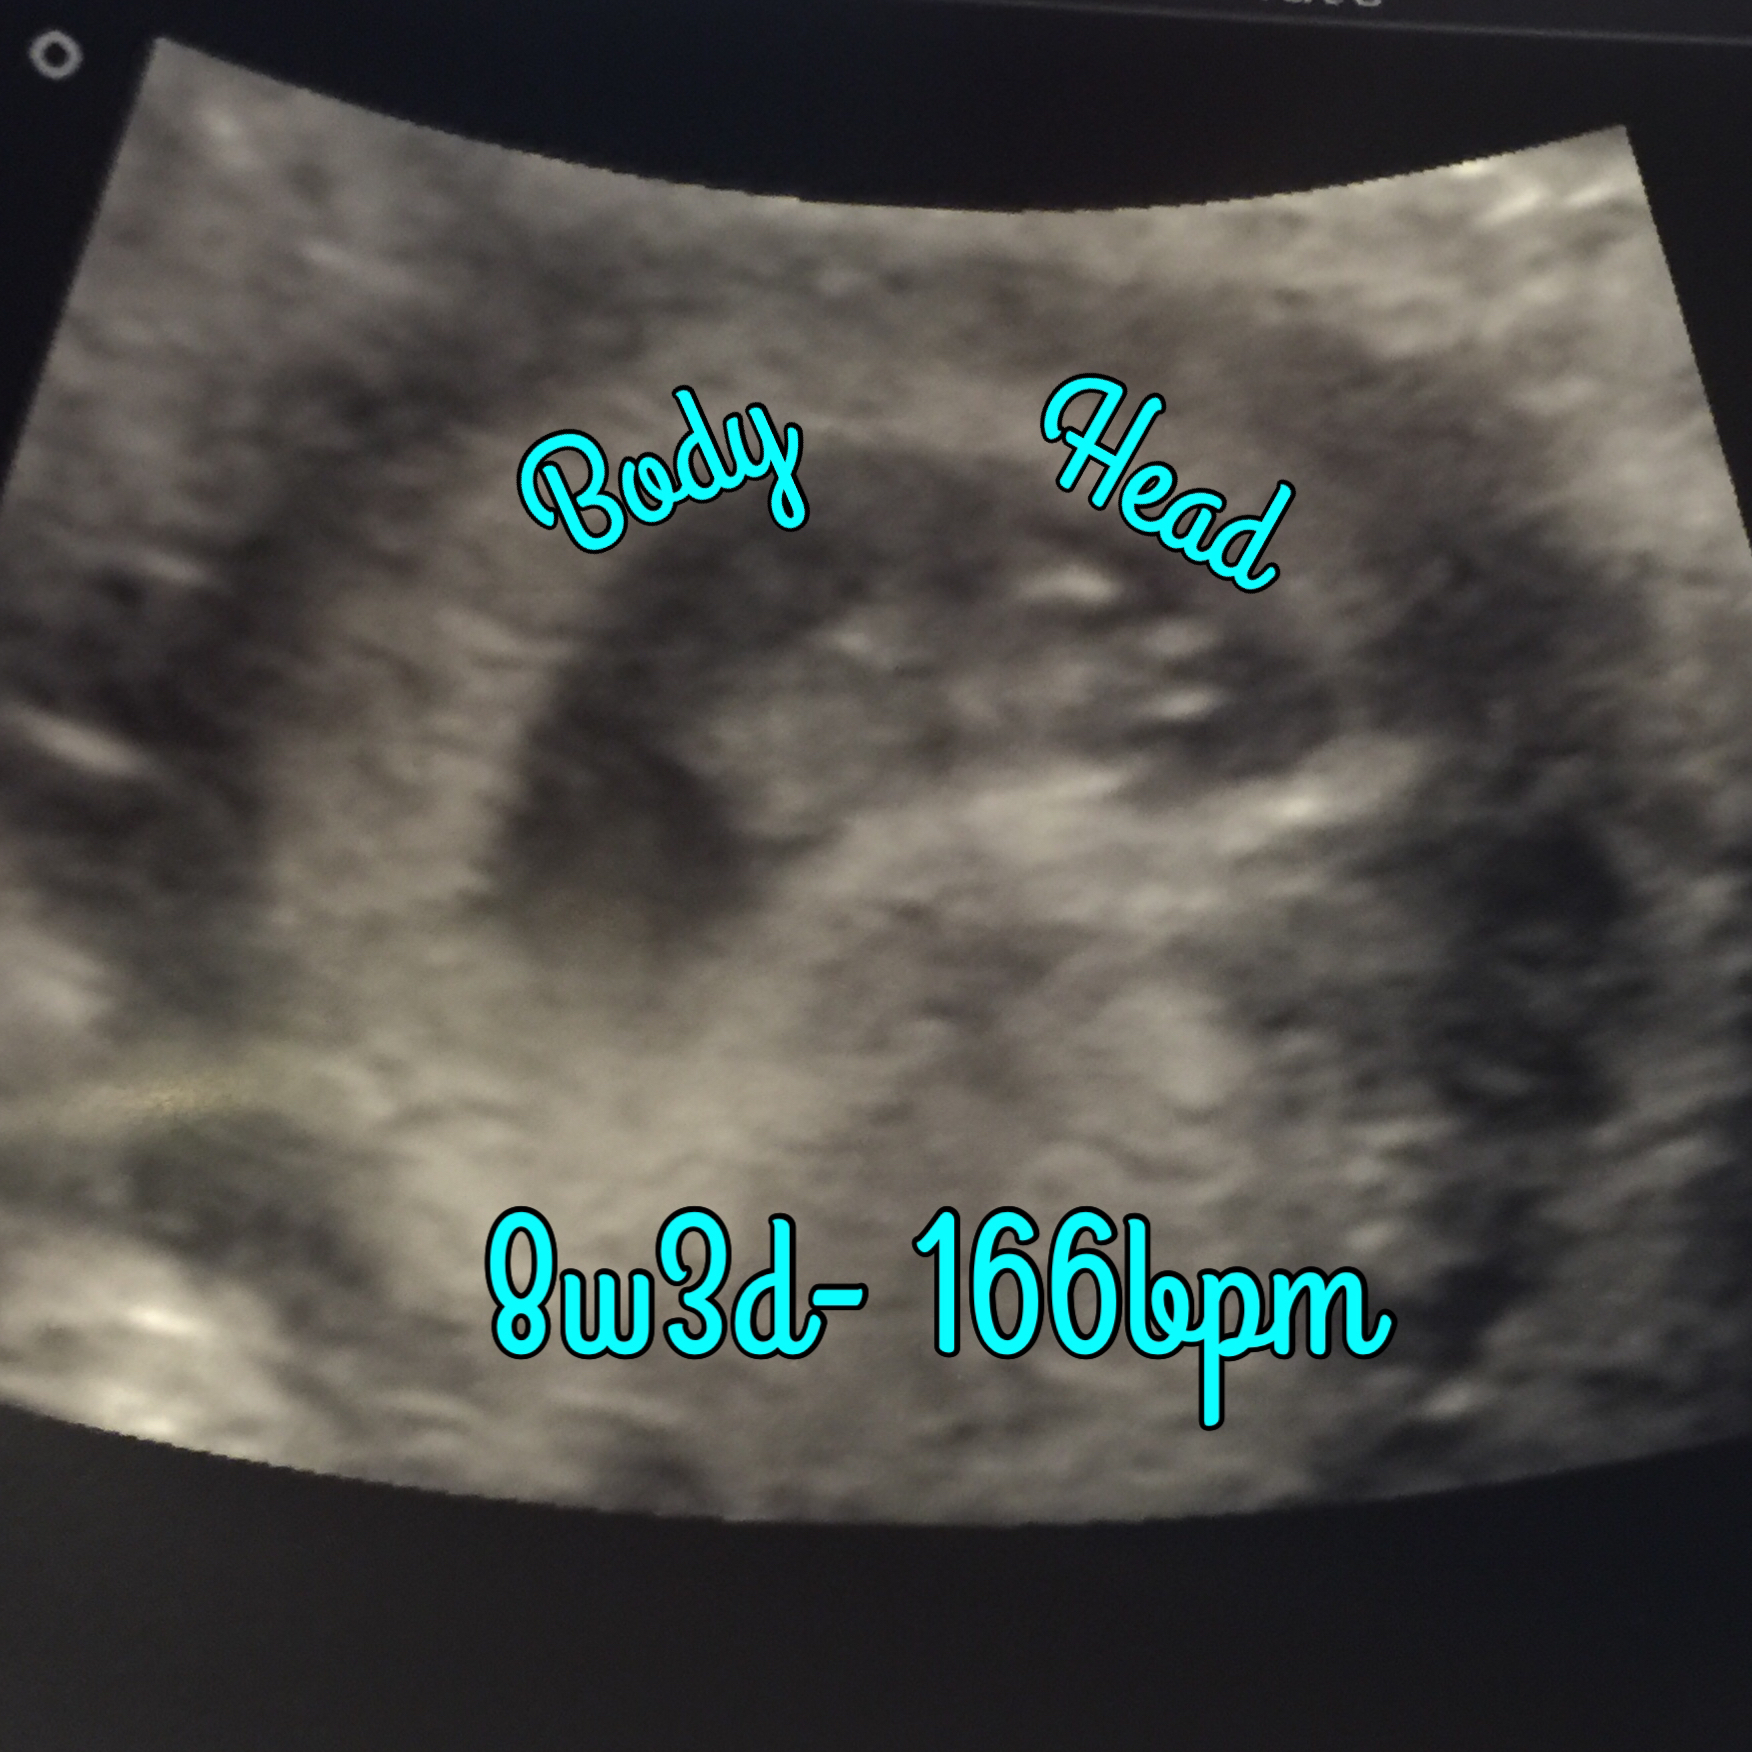

I can't believe this is real!!! Just got done with our first ultrasound awwwww. My little gummy bear with three weird antennas sticking out of his head lol. Due June 6th. I'm 8w3d here. Eek!

I was estimating that I was 8wk3da based off lmp, or 8wk5da based on when I ovulated (i was temping). Baby measured right at 8wk4da, so smack in the middle!